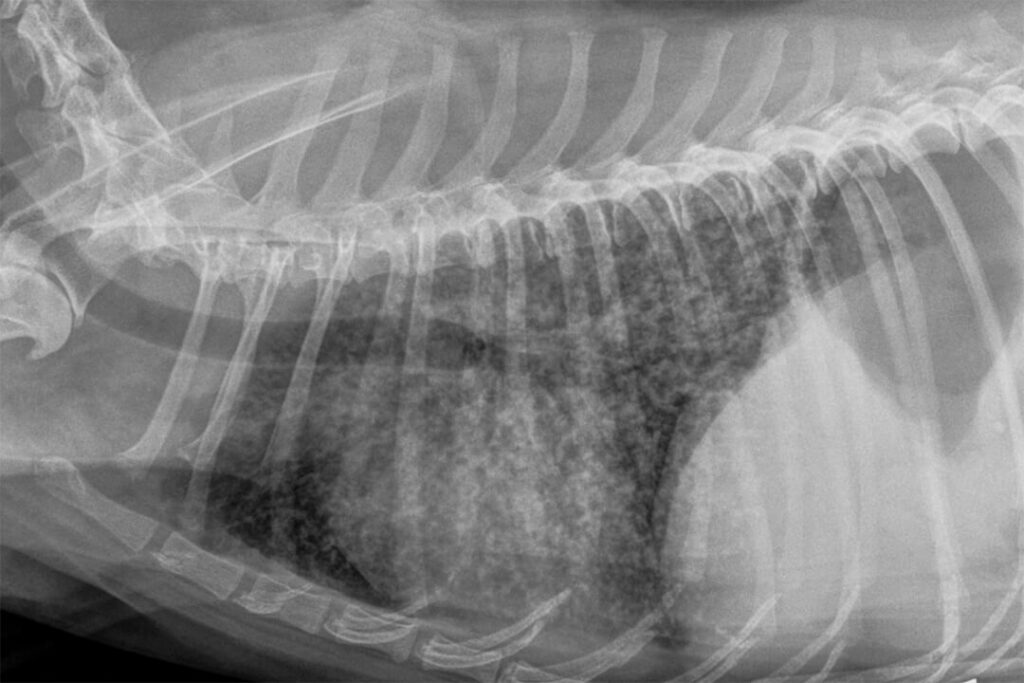

Lung; cat No. 1. Diffuse, severe bronchointerstitial pattern Cat Lung Damage In its early stages, chronic bronchitis causes inflammation in the small airways. Pneumothorax is an accumulation of air outside the lungs, but inside the chest wall. Persistent inflammation will cause blockage of the. Respiratory diseases are common in cats. Fletcher, “are asthma and its acute exacerbation; How does chronic bronchitis affect a cat's lungs? Cat lung problems refer to various. Cat Lung Damage.